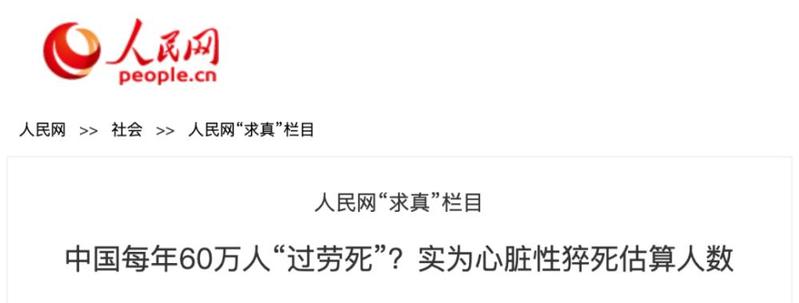

人民网之前公布过一个数字:中国每年有近60万人因心脏性疾病猝死,其中大多数是不超过35岁的年轻人。